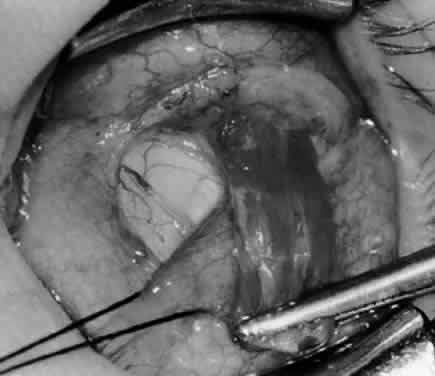

Fig. 3. The eye is retracted superonasally with the 4-0 silk traction suture. The suture is attached to the drapes with a hemostat. A Stevens hook is placed along the inferior border of the lateral rectus muscle and drawn temporally. A von Graefe hook is placed within the incision and drawn inferotemporally to expose the inferior oblique muscle.

Fig. 4. A stiff iris repositor can be placed against the sclera to depress the sclera and enhance the view of the inferior oblique muscle. The inferior temporal vortex vein adjacent to the Stevens hook is retracting tissue along the inferior border of the lateral rectus muscle. The second Stevens hook is pointing to the inferior oblique muscle.